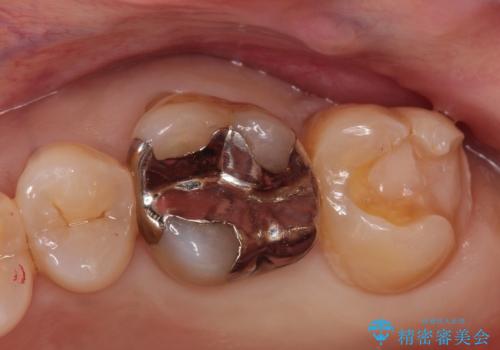

銀の詰め物が外れた。プラチナゴールドインレー

- 銀の詰め物が外れたことを主訴に来院されました。

適合の良い修復を希望されましたので、プラチナゴールドインレーにて治療を行っております。

PGA(プラチナゴールド)インレーは適合もよく、壊れるリスクも極めて少ない修復です。